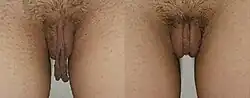

Schaamlipverkleining (ook schaamlipcorrectie, labiumreductie, labiaplastiek of labioplastiek) is een cosmetisch-chirurgische ingreep waarbij de binnenste schaamlippen worden verkleind of geheel verwijderd. Soms worden ook de buitenste schaamlippen verkleind, en/of wordt de clitorishoed verkleind.

Bij een labiaplastiek worden, meestal onder plaatselijke verdoving, overtollig weefsel c.q. slijmvlies verwijderd. Dit kan op verschillende manieren plaatsvinden:

- Via laterale excisie. Hierbij wordt slijmvlies over de hele lengte van de schaamlip weggesneden. Dit wordt gedaan bij veel overtollig weefsel of wanneer sprake is van hyperpigmentatie.[2] Dit is relatief de eenvoudigste ingreep, maar geeft vaak een wat kunstmatig resultaat, doordat het natuurlijke aspect van de randen van de schaamlippen verloren gaat.

- Via wigexcisie waarbij een driehoekje van overtollig schaamlipweefsel wordt weggehaald.

- Een variant hierop is de Z-plastiek, waarbij de wond niet in een rechte lijn maar in een zigzag wordt gesloten. Dit is een iets complexere techniek, maar heeft doorgaans een wat fraaier resultaat.

- De-epithelialisatie: hierbij wordt een centraal deel van de binnen- en/of buitenzijde van de schaamlip verwijderd. Dit is een ingewikkelde techniek die maar weinig wordt toegepast.

De meeste patiënten verlaten op dezelfde dag het ziekenhuis. Het eindresultaat wordt na zes tot negen weken bereikt. Mogelijke complicaties zijn infecties, nabloedingen en littekens.[5][9]